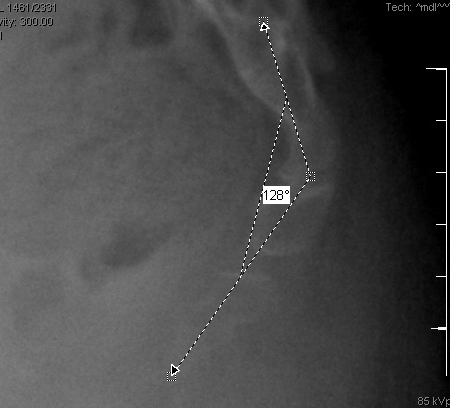

A instabilidade radiográfica, evidenciada por subluxação posterior e hipermobilidade (>20° de angulação sacrococcígea ou intercoccígea), é observada em cerca de 70% dos pacientes.[16][21][Figure caption and citation for the preceding image starts]: Radiografia sacrococcígea lateral dinâmica de um paciente com coccigodinia crônica idiopática, mostrando 30° de flexão anterior na posição ortostáticaDo acervo pessoal do Dr. R. Schrot [Citation ends].

[Figure caption and citation for the preceding image starts]: Radiografia sacrococcígea lateral dinâmica de um paciente com coccigodinia crônica idiopática, mostrando 30° de flexão anterior na posição sentadaDo acervo pessoal do Dr. R. Schrot [Citation ends].